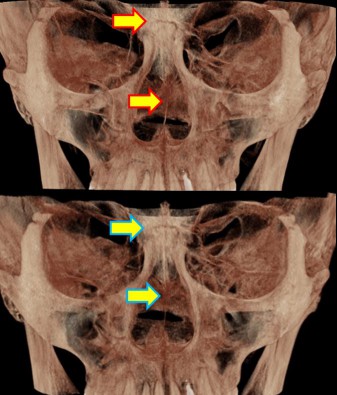

There are many around the world—including in Korea—who claim not only to treat TMJ or craniofacial structures, but to treat systemic disorders. Most of them use applied kinesiology for diagnosis and treatment. I myself served for five years as a dental director in a Korean applied kinesiology organization. It is a good discipline. Yet many people—including in Korea—have not gone beyond the level of using applied kinesiology. For example, in the case of the TMJ: applied kinesiology can determine which side of the joint is problematic, and can evaluate how effective a TMJ device is. However, it cannot reveal the direction of asymmetry between the right and left TMJs, or the detailed joint motion. The way to know those is through osteopathic medicine. In Korea, there is almost no practice of osteopathy. 99% of the population do not know the word “osteopath,” and few have experienced osteopathic treatment. It takes a long time to understand the motility of the TMJ.

I have devoted my life to performing orthodontic treatment for people with TMJ problems. Even in the United States, where osteopathy was born and has developed, it seems that almost no one applies the concept of osteopathy when fabricating splints for the TMJ.

Dentistry still remains dominated by the concept of CR (Centric Relation). Many osteopathic physicians have long claimed that the temporal bones move, and treat on that basis, yet the mainstream thinking has not changed. Many dentists still believe that if the mandible (lower jaw) is asymmetric or if the lengths on the right and left differ, surgery is required, and they in fact treat by surgery.